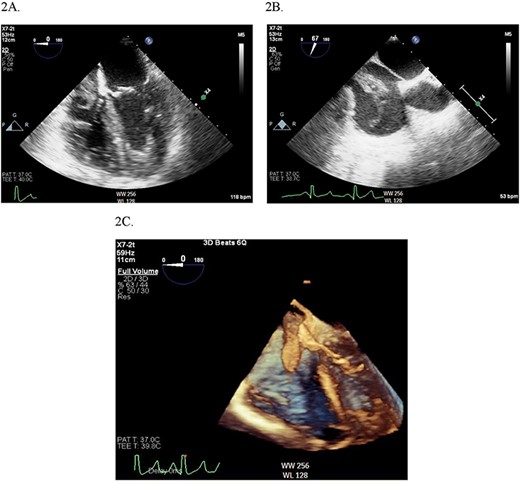

2D (A) and 3D (B) illustration of the IVC thrombus in long and short-axis views.